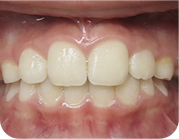

adult invisalign

Corrected with without surgery using invisalign

Before

After